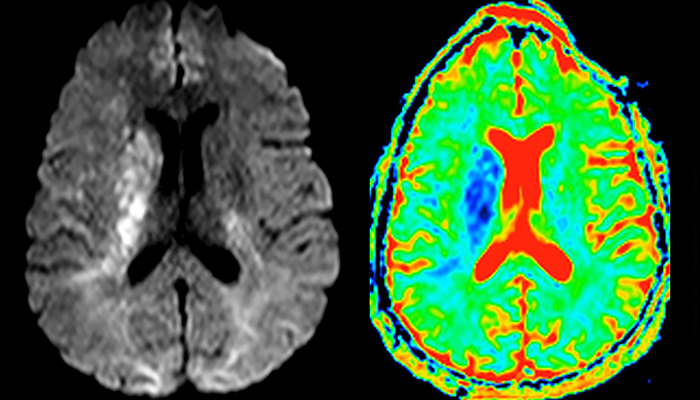

Every minute counts in stroke imaging

“In France, stroke is usually imaged with MRI, not CT, even for emergency treatment. This is because MRI helps us directly visualize ischemia in the acute phase, but can also help rule out differentials such as MS and hematoma. In addition, we can assess the intracranial and extracranial vessels during the same examination,” says Dr. Savatovsky.

The first challenge in MRI of stroke is speed. The patient typically arrives from an ambulance in the MRI preparation room and the installation is done on a separate dock outside the scanner room. “The venous access is placed during the neurological examination. If the delay from the first symptoms allows the patient to receive thrombolysis we do a very fast examination that typically lasts about 11 minutes including the pre-scans. In the case of transient ischemic stroke we usually add ASL perfusion because in some symptoms with negative diffusion, ASL sometimes indicates a vascular origin.”

“Ingenia provides great flexibility in the parameters setting. We can tune a sequence the way we want,” says Dr. Savatovsky. “For example, in a stroke exam we use a FLAIR sequence of about two minutes instead of the four-minute FLAIR we use for MS. The diffusion is 30 seconds, the T2*-weighted scan is 30 seconds, the angiography scan time is less than one minute. Ingenia is a great scanner in that situation; even with these fast sequences we can achieve good images with good SNR. When the first sequence tells us that it’s not an ischemic stroke but a hemorrhagic stroke, we may switch to a time-resolved angiography to look for vascular malformations and venous thrombosis.

The ideal stroke protocol?

“Every center is different, but for me the ideal protocol for stroke includes diffusion weighted imaging, FLAIR, and fast susceptibility imaging,” says Dr. Savatovsky. “Our fast susceptibility weighted imaging takes 50 seconds, so it’s as fast as T2*-weighted imaging. It visualizes hemorrhage but also the clots. We also do 3D MR angiography that provides information on cervical and brain vessels. If the patient does not need immediate treatment, or if additional information is needed to decide on treatment, we might also add perfusion imaging and post-contrast T1-weighted imaging.”